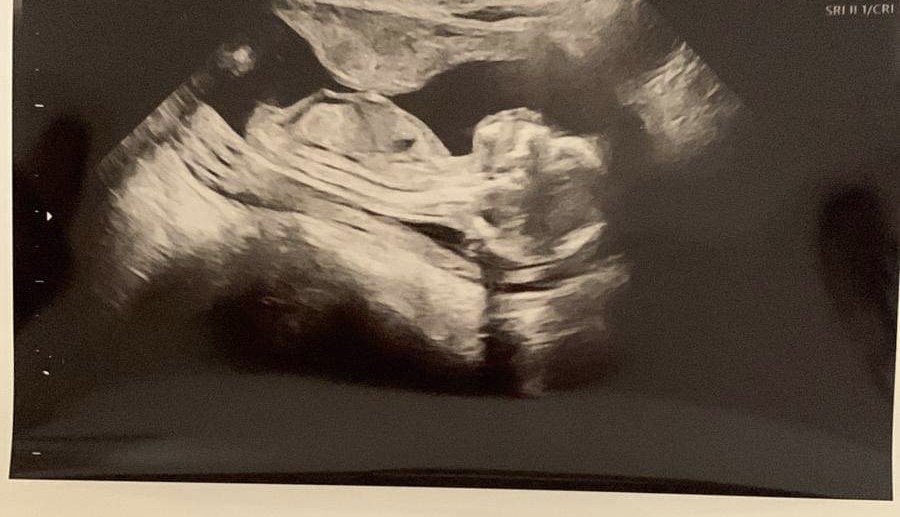

Je to dievčatko alebo chlapček?

@kikatina14 dá sa to určiť podľa pohlavného hrbolku, asi preto sa pýtaš, že? 🙂 plus ešte niekto vie aj podľa tvaru hlavičky. Mne by to podľa toho vychádzalo na dievčatko, ale ber to s nadhľadom... 😊

@nelca84 hmm a podla mna na 50% chlapec :D a teraz že koho veštecka gula je viac spolahliva :D